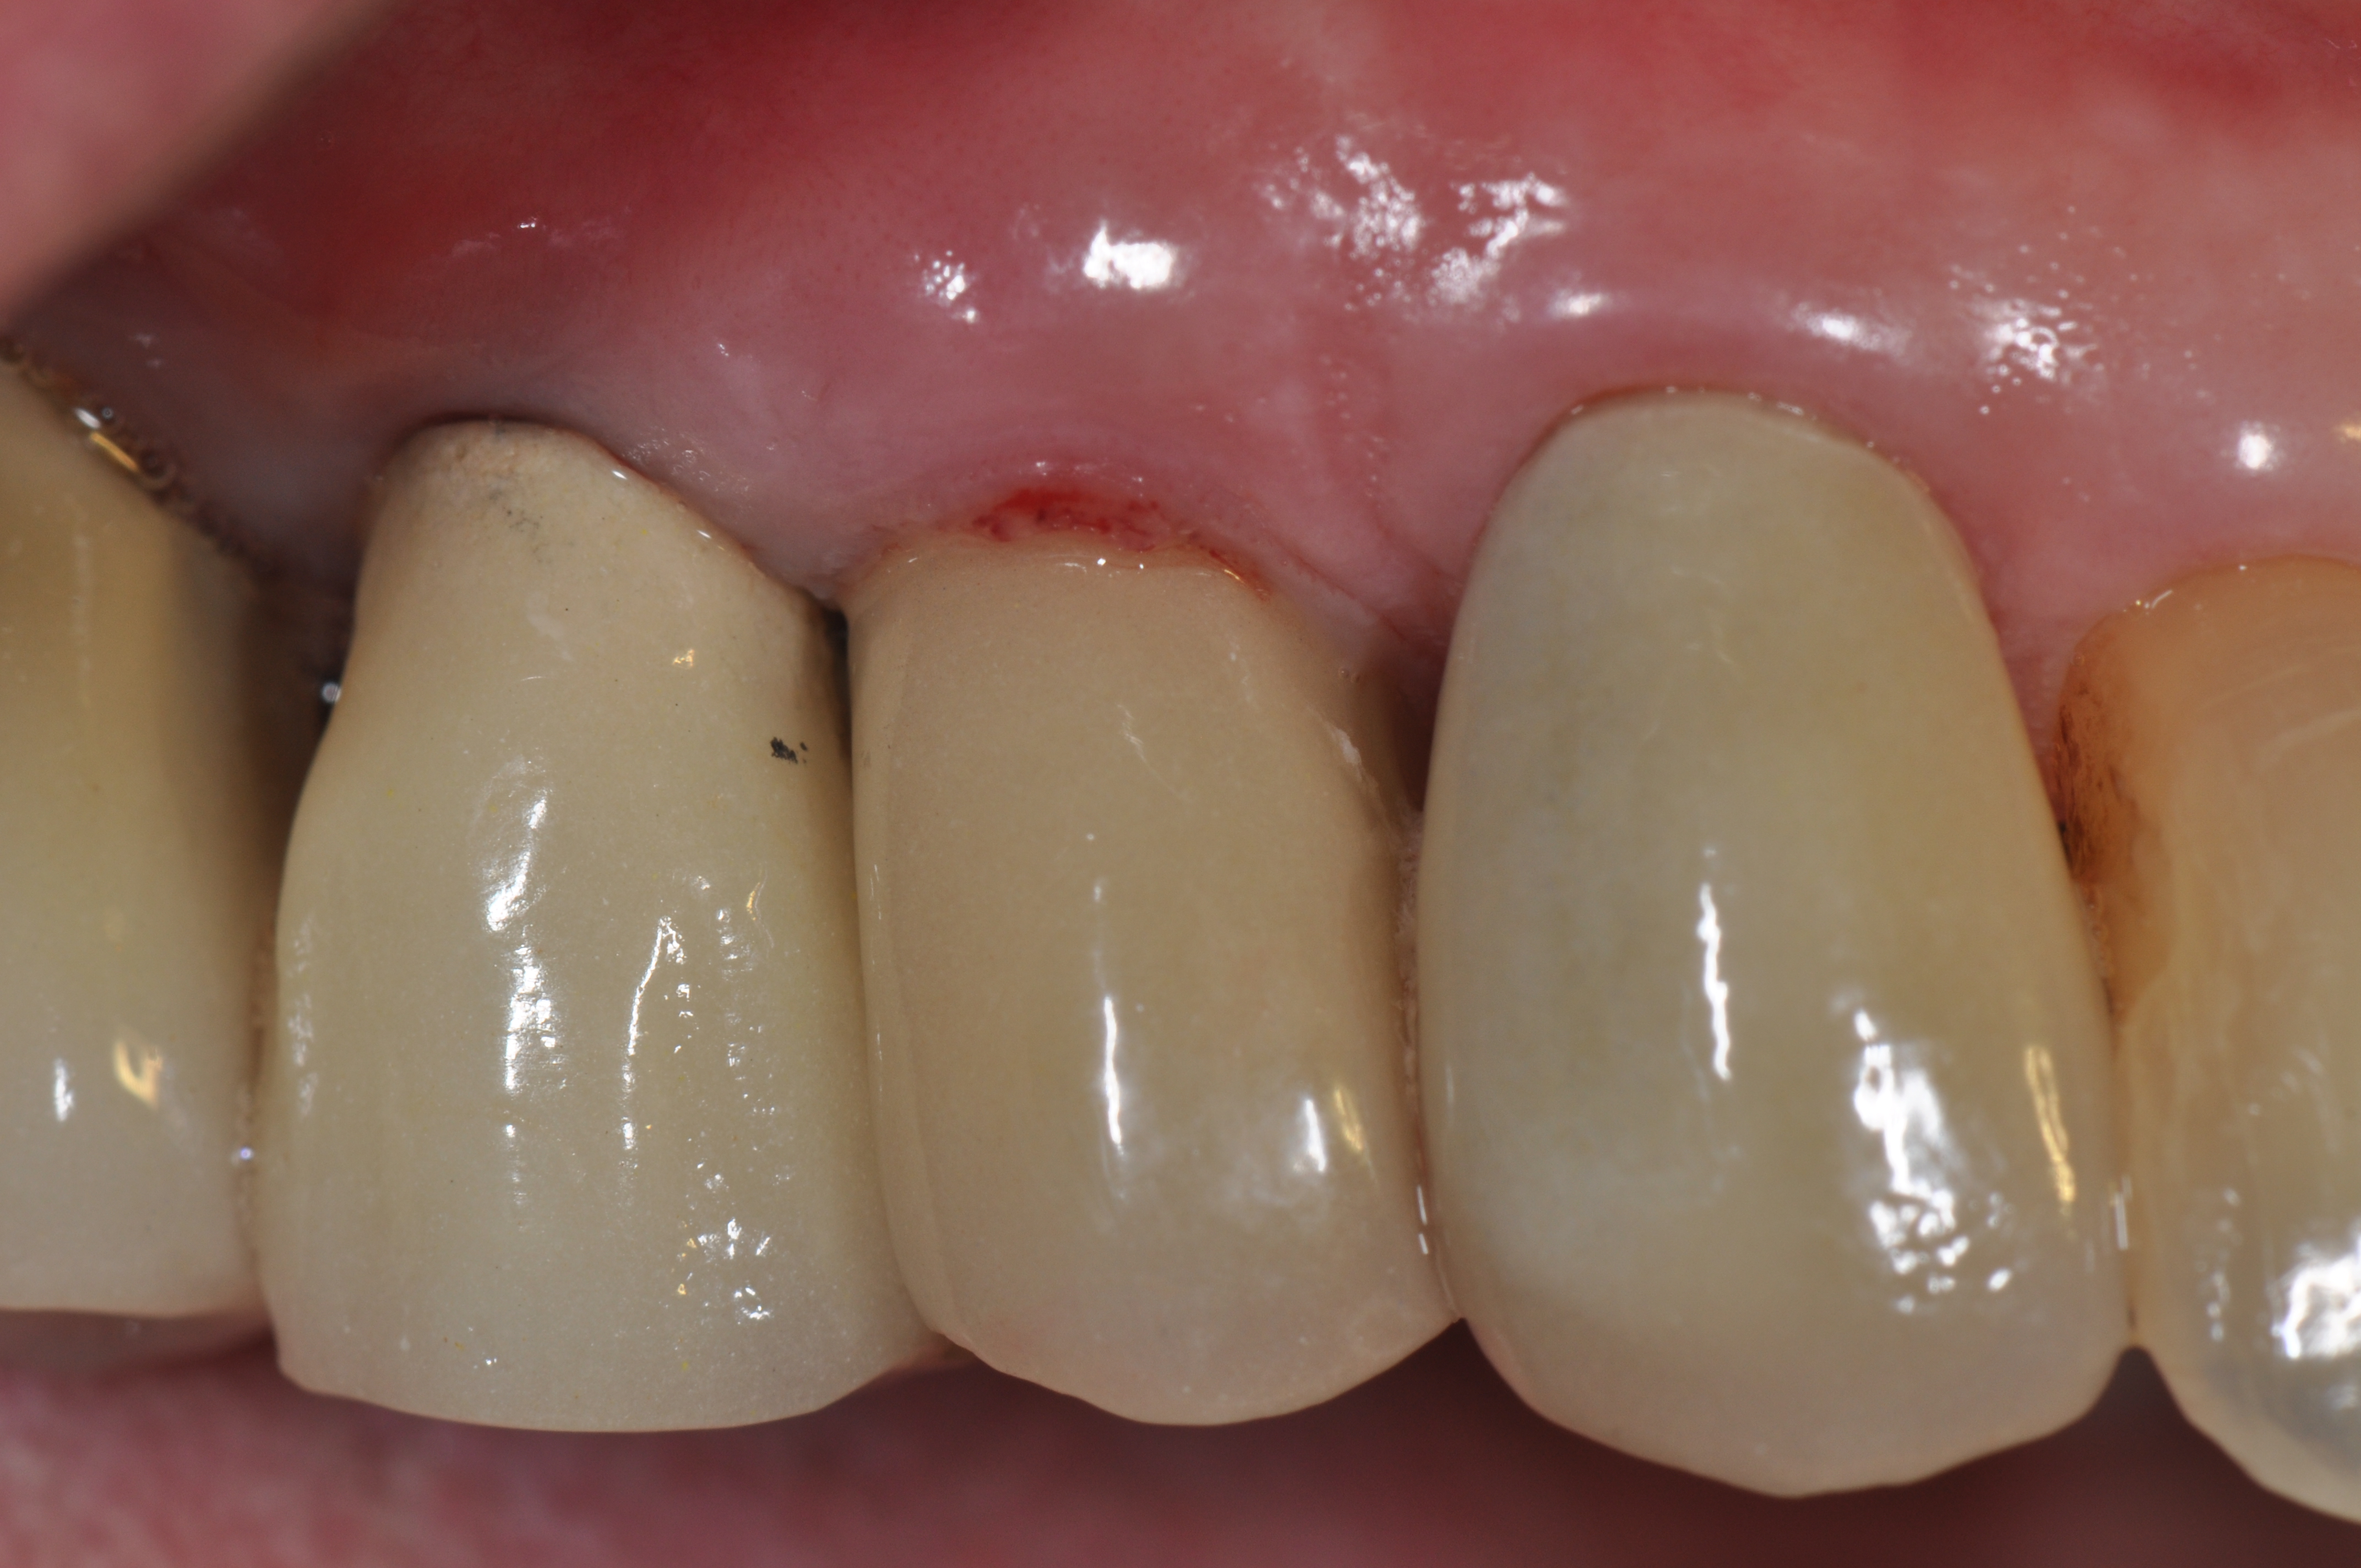

Fig 6. A clinical view of this area suggests that peri-implant mucositis is present. The tissue is swollen, it bleeds on probing, has 5 mm of probing depth, and exhibits purulent exudate.

Figure 6

Fig 7. Eight weeks after nonsurgical treatment that involved scaling of the area, which removed cement, and irrigation with an anti-inflammatory hydrogel, the area is healthy. No BOP is present, purulence is absent, and probing depths have been reduced to 4 mm as a result of the reduction in inflammation.

Figure 7